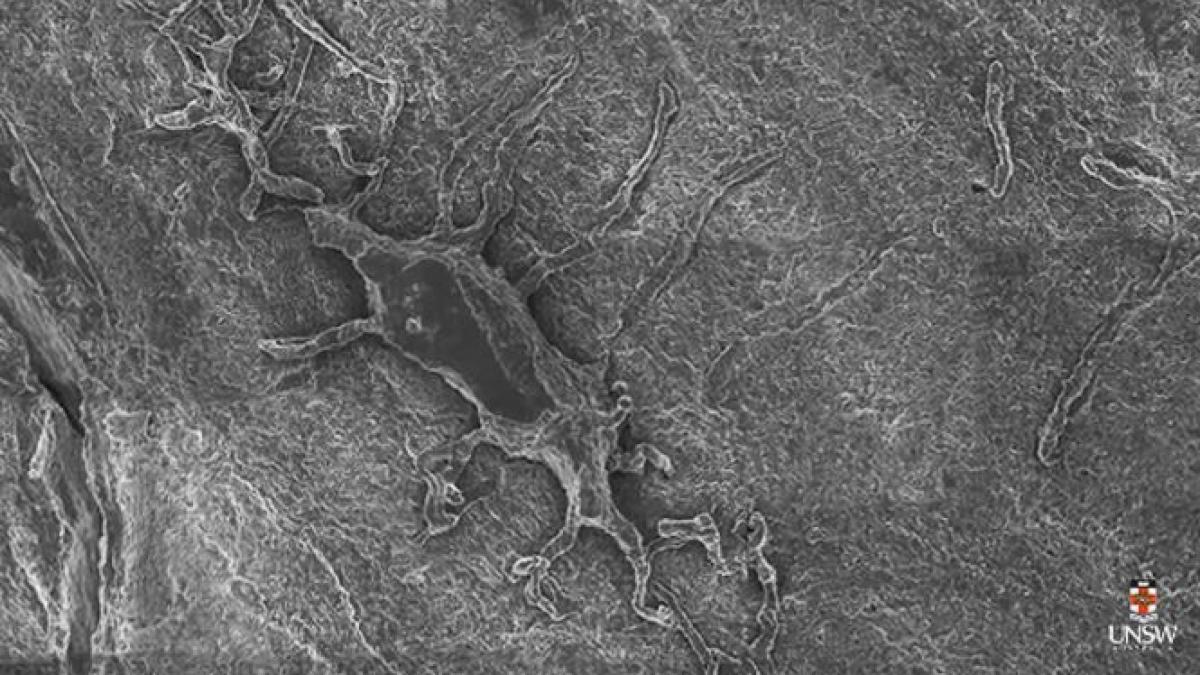

Google Maps pentru corpul uman, prima tehnologie care permite explorarea organismului până la nivelul celulelor03 Apr